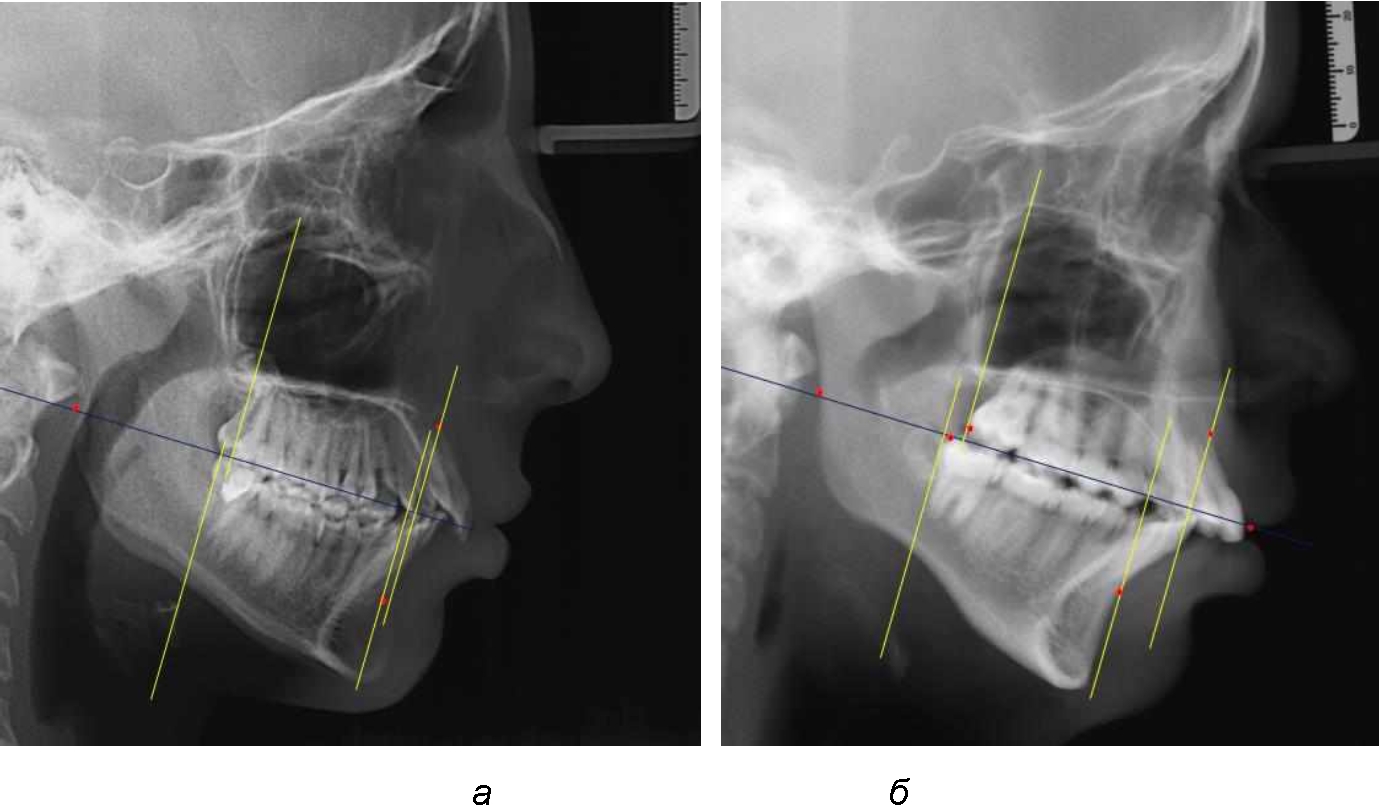

На рентенограммах с признаками дистальной окклюзии Wits-число имело положительные значения. Дистальная точка нижнего моляра была расположена позади верхней дистальной точки окклюзии второго моляра. Относительно равными, так же как и при анализе снимков с мезиальной окклюзией, считались показатели альвеолярно-дентальных размеров, при которых разница не превышала 1,5 мм. Тем не менее расстояние «rmРOcP-A(SS)» превышало расстояние «rmРOcP-B(SM)» в среднем по группе на (5,29 ± 1,47) мм (рис. 4).

Рис. 4. Положение апикальных точек и челюстей при дистальной окклюзии с равными (а) и разными (б) альвеолярно-дентальными размерами зубочелюстных дуг

В тех случаях, когда при дистальной окклюзии альвеолярно-дентальные размеры были различными, размер нижней челюсти превышал аналогичный параметр верхней челюсти, в среднем на (3,62 ± 1,12) мм.